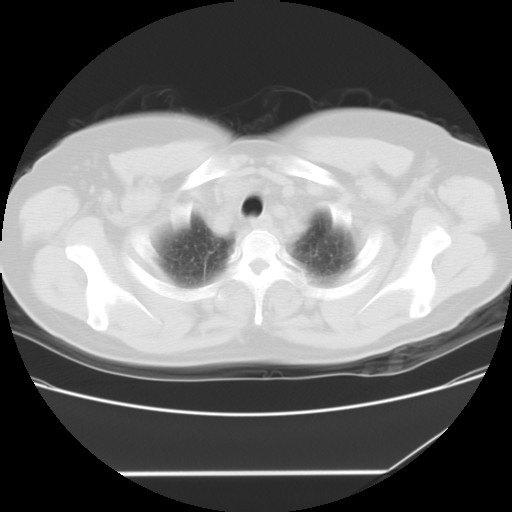

标题: CT24018:女性,62岁,咳嗽4年,无热,胸部CT扫 [打印本页]

女性,62岁,长期咳嗽,既往从事工作有粉尘接触,有高血压病史,110/150mmhg,近日咳嗽加重,脸面浮肿,请大家帮看下,

1、尘肺;2、慢性支气管炎合并肺部感染;3、心影增大(左房、左室大),考虑高血压性心脏病。

心包有积液吗?

慢支并肺部炎症;右肺结核球?主肺动脉、右肺动脉影不宽,右心室不大,不支持肺心病;无心包积液。